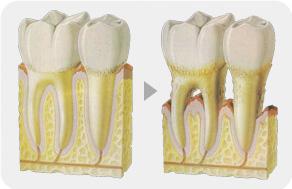

前后对比

牙龈萎缩主要分为病理性牙龈萎缩和生理性牙龈萎缩两类,病理性牙龈萎缩主要是因为在患者的龈缘部分有牙结石存在,但又长时间的不能得到有效的清理,各种细菌滋生刺激而引发的病理性牙龈萎缩。

随着年龄的增长,牙齿部位也随着年龄的逐渐增大,出现萎缩,导致牙齿根部暴露,这种导致牙龈萎缩的现象称为生理性牙龈萎缩。

牙根暴露